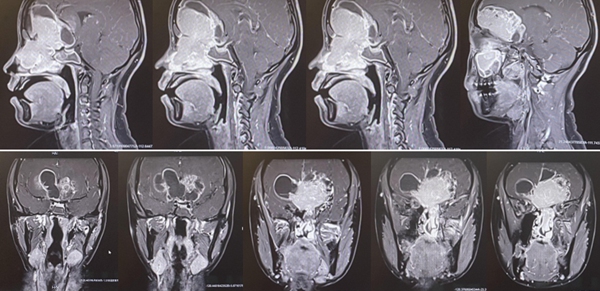

從術后磁共振和CT檢查看到,腫瘤已經被全切,腦組織恢復很完美,顱底使用鈦板修復。重慶醫科大學附屬第二醫院供圖

順利完成手術后,小于很快轉出ICU,回到了普通病房。但是,這并不代表手術取得了最終勝利。由于切除腫瘤后顱底缺損非常巨大,雖然做了充分準備,并嚴密修補,但術后仍可能發生低流量的腦脊液滲漏,存在嚴重顱底感染的風險。所幸,通過反復支撐、換藥,小于的顱底終于在術后2個月的時候完全愈合。